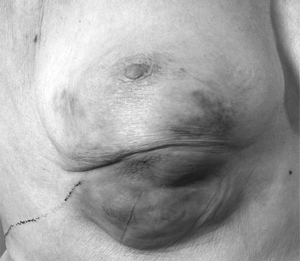

Neoadjuvant endocrine therapy can be used in many postmenopausal women with larger tumours to avoid mastectomy, and to render operable those tumours that are locally advanced at diagnosis and not suitable for surgery. The optimal duration of treatment remains unclear, but current evidence suggests that tumour shrinkage with agents such as letrozole continues beyond 3–4 months, and treatment can be continued until the cancer has shrunk sufficiently either to become operable or to allow breast-conserving surgery (Box 5).

5 Use of neoadjuvant endocrine therapy in tumour shrinkage and breast conservation

![]() Locally advanced right breast cancer. |

![]() After 9 months neoadjuvant endocrine therapy with letrozole. |

![]() After conservative surgery to the right breast. |

Photos provided by J M Dixon.